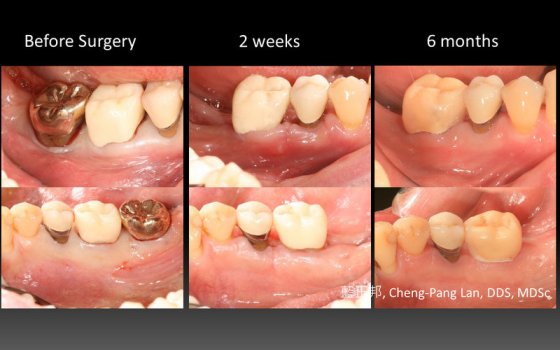

●第八章就是Buser最著名的Early implant placement in the esthetic zone,完整分類風險等級、挑選案例、單顆植體、多顆植體的前牙手術考量。更加入了超過十年的術後追蹤。我認爲Buser在這塊領域的貢獻非凡,是整本書的精華所在。